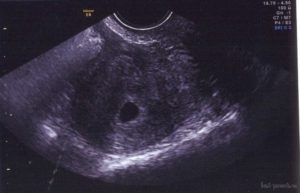

На третьей неделе беременности (пятой акушерской неделе) в большинстве случаев в полости матки визуализируется плодное яйцо.

Оно представляет собой анэхогенное образование круглой или овальной формы с ободком повышенной эхогенности.

Располагается чаще всего плодное яйцо в одном из трубных углов матки, намного реже его можно найти ниже. В плодном яйце визуализируется эмбрион длиной 2-4 мм.

В случае когда плодное яйцо закреплено в маточной полости, на экране монитора видно темное пятно. Доктор производит замер СДВ. Данная аббревиатура означает средний внутренний диаметр плодного яйца.

Акушерский срок в 5 недель приблизительно соответствует трехнедельному эмбриональному. Диаметр яйца будет около 0,5 сантиметра. Размер расположенного в нем эмбриона составляет в среднем 0,3 см.

Развивается околоплодный желтый мешочек, незаменимый для питания эмбриона.